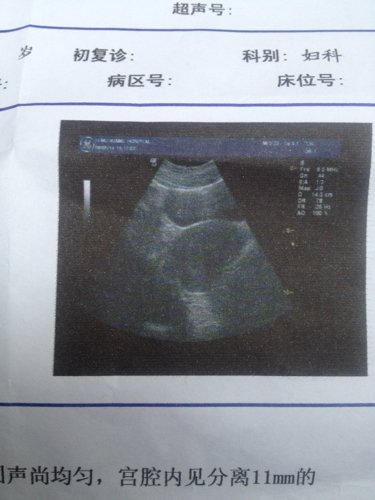

医生给开的两盒新生化颗粒已经喝完了,药流第六天的B超图,医生说有积血,我可以再买新生化颗粒吃么??

医生给开的两盒新生化颗粒已经喝完了,药流第六天的B超图,医生说有积血,我可以再买新生化颗粒吃么???反正胚胎是排出来的,不碍事吧????

病情分析: 你好,根据你的b超检查看有少量的宫腔积血,问题不大,可以继续服用新生化颗粒或益母草颗粒促进子宫收缩。 指导意见: 建议你注意休息,适当的活动,避免久躺久坐,休息时侧卧位,有助于淤血排除。